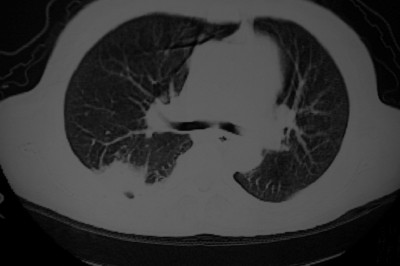

以下是引用天南地北在2007-4-10 1:49:00的发言:[br]考虑右下叶周围型肺癌伴肋骨转移。

以下是引用jone-baby在2007-4-10 8:45:00的发言:[br][br] [br] 患者[br]有发热史,x线片考虑肺脓肿.肺脓肿可以导致肋骨破坏吗?[br]脓肿可以排除吗? [br] [br] [br]

以下是引用林建春在2007-4-10 7:35:00的发言:[br]周围型肺癌侵犯肋骨

以下是引用liuyue在2007-4-10 7:56:00的发言:[br]周围型肺癌侵犯肋骨,左肺转移。

以下是引用zhangzhongshou在2007-4-10 10:24:00的发言:[br]右肺下叶背段厚壁空洞,伴胸膜改变、肋骨破坏,其内可见死骨、周围骨质硬化,左肺可见小结节影,[br]单纯影像学更支持结核。建议进一步检查。